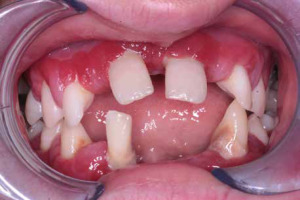

When he was 5 years of age the intraoral examination revealed incomplete primary dentition with five missing teeth, marginal gingivitis, interdental papilla hypertrophy, carious lesions in seven primary teeth, and one permanent tooth of various degrees of advancement for conservative treatment (Fig. 1). The patient was qualified for simultaneous dental treatment under general anesthesia. A panoramic radiograph picture was taken showing the advanced destruction of the alveolar bone in the maxilla and the alveolar part of the mandible. Three primary teeth were completely devoid of bone base. The roots of the lower incisors were only half of their normal length (Fig. 2). Under antibiotic protection (amoxicillin with clavulanic acid at a dose of 30 mg/kg), professional removal of dental plaque and conservative treatment of teeth extraction of four primary teeth with complicated caries and periodontitis were performed. The patient was provided with permanent dental care.